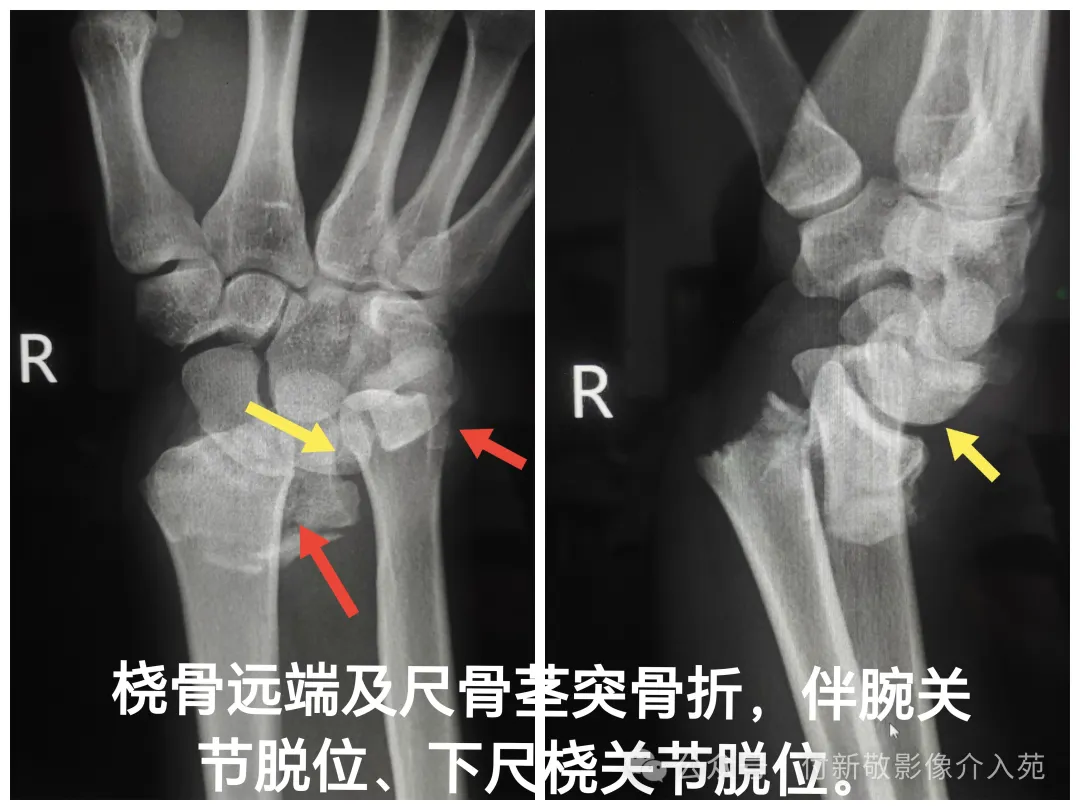

五、腕关节脱位

腕关节脱位:手腕在屈腕状态下遭受较大冲击力,如高处跌落、摔倒、车祸时等,使着力点集中于头月关节,致使头月骨周围的掌背侧韧带发生断裂,发生尺桡骨远端骨折和腕关节及腕骨脱位。

患侧腕部明显肿胀疼痛,手腕关节活动功能丧失,伤及神经时,可有神经分布区麻木感。

腕关节X线检查:首选检查,可明确诊断腕关节组成骨及诸腕骨是否存在脱位及骨折情况。